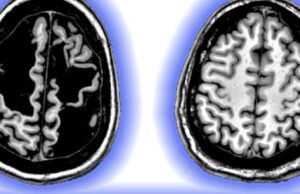

Paradoxul creierului lui Daniel Carr

Se spune de multe ori că ficatul este singurul organ care are capacitatea de a se regenera. Însă și creierul are o astfel de...